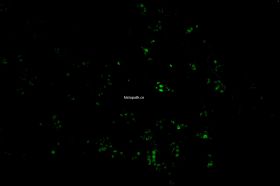

TUNEL染色荧光法

TUNEL检测原理:

细胞在发生凋亡时,会激活一些DNA内切酶,这些内切酶会切断核小体间的基因组DNA。细胞凋亡时抽提DNA进行电泳检测,可以发现180-200bp的DNA  ladder。基因组DN A断裂时,暴露的3'-OH可以在末端脱氧核苷酸转移酶(Terminal Deoxynucleotidyl TransferaseTT)的催化下加上绿色荧光探针荧光素(FITC)标记的dUTP(fluorescein-dUTP),从而可以通过荧光显微镜或流式细胞仪进行检测,这就是TUNEL(T dT-mediated dUTP Nick-End Labeling)法检测细胞凋亡的原理。